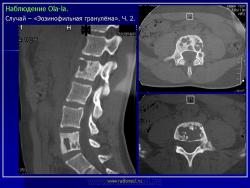

Тело позвонка является наиболее часто поражающейся частью позвоночника. Ранние поражения проявляются, как литические очаги.

Формируется «VERTEBRA PLANA», что может привести к боли и значительным неврологическим расстройствам.

LCH у 17-летней девочки с болями в спине.

На КТ изображении визуализируется неправильной формы литическая деструкция тела позвонка (стрелка).